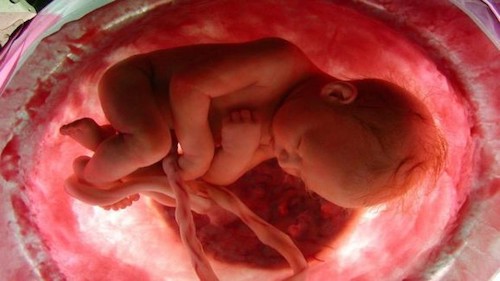

Las partículas se encontraron en las placentas de cuatro mujeres sanas que tuvieron embarazos y partos normales. Se detectaron microplásticos tanto en la parte fetal como materna de la placenta y en la membrana dentro de la cual se desarrolla el feto.

Los microplásticos tenían en su mayoría un tamaño de 10 micras (0,01 mm), lo que significa que son lo suficientemente pequeños como para ser transportados por el torrente sanguíneo. Es posible que las partículas hayan entrado en los cuerpos de los bebés, pero los investigadores no pudieron evaluar este aspecto.

Los efectos potenciales de los microplásticos en los fetos incluyen un crecimiento fetal reducido. Las partículas no se encontraron en las placentas de otras dos mujeres en el estudio, lo que puede ser el resultado de una fisiología, dieta o estilo de vida diferente, según los investigadores.